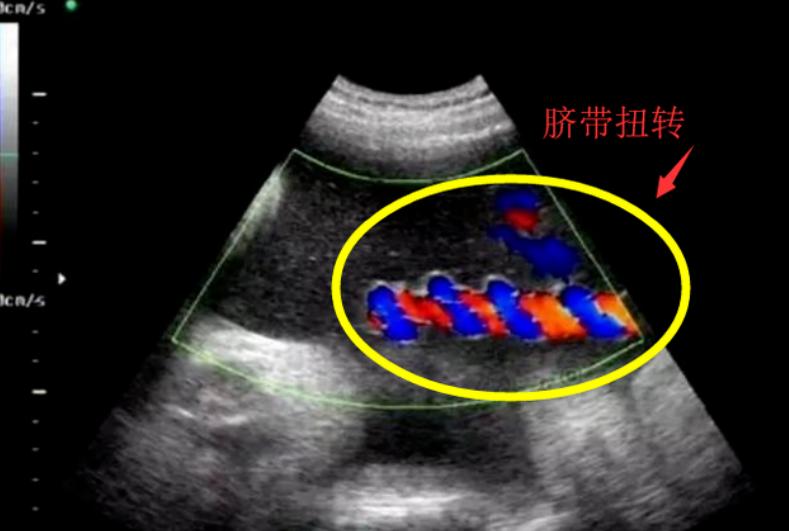

之前网上热传一个真实事件:一位孕妈产检时发现胎儿脐带可能严重扭转,医生紧急手术。

取出宝宝时,所有人都倒吸一口凉气,脐带紧紧缠绕在孩子身上,扭转圈数将近六十圈!

肚皮部位已经因缺血发紫。

万幸,宝宝出生后检查正常,但这一幕让无数人直呼“太惊险”。